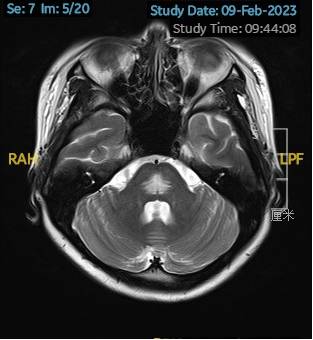

2023.03.27颅脑MR平扫示双侧基底节区及桥脑异常信号,考虑渗透性脱髓鞘综合征,较前范围略减小,请结合临床,见图4。

图4 2023.03.27双侧基底节区及桥脑见对称性片样长T1长T2信号,FLAIR呈高信号,较2023-02-24MR所示范围减小。脑室、脑池、脑沟、脑裂未见明显异常,中线结构居中。